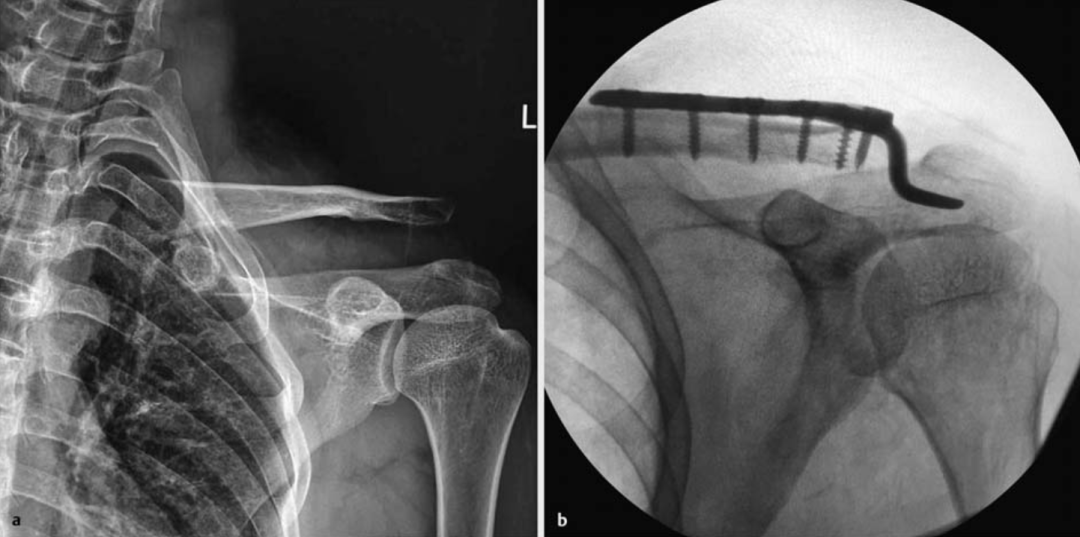

▲ 图示肩锁关节脱位,及钩钢板固定后的影像。(图源:10.1055/a-0946-2886)

肩锁关节脱位是临床常见的肩部损伤,常见于直接暴力。Rockwood III度及以上的肩锁关节脱位,由于喙锁韧带与肩锁韧带的完全断裂,脱位复位与维持困难,通常建议手术治疗。在内固定方式上,尽管Tightrope、袢钢板及韧带重建等新技术不断涌现,但锁骨远端钩钢板基于其稳定的固定、确切的疗效,目前仍是内固定治疗肩锁关节脱位的金标准。